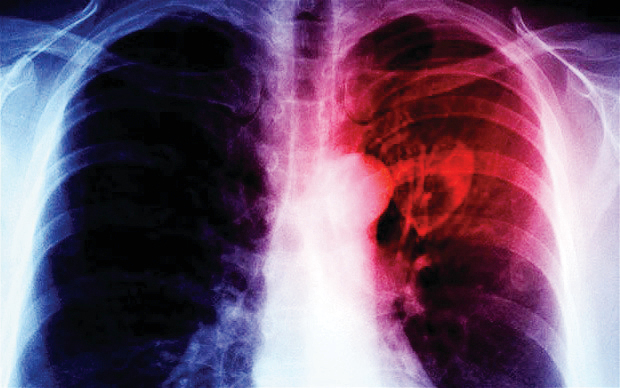

أشارت دراسة بريطانية إلى إمكانية تفادي ثلث حالات توقف القلب ومحاولات الإنعاش في المستشفيات، وذلك من خلال تقييم الأطباء للمرضى بشكل أفضل.

وأظهرت الدراسة، التي شملت أكثر من 500 مريض توقفت قلوبهم أثناء وجودهم في المستشفى، أن توقف القلب، في كثير من الحالات، كان يمكن ألا يحدث في ظل رعاية أفضل. كما وجدت أن الأطباء لم يدركوا علامات التحذير التي تشير إلى تدهور صحة المرضى في ثلث الحالات.

وفي 10 % من الحالات، تمت محاولة الإنعاش القلبي الرئوي على الرغم من أن المرضى أو أطباءهم كانوا قد قرروا بالفعل عدم الحاجة إليها، وهو ما يعني أن المرضى تعرضوا بلا داع لمحاولات إنعاش «غير مبررة» فيما كان يجب أن يسمح لهم بأن يموتوا بسلام.